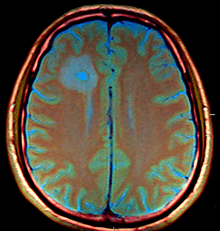

The diagnosis is established by a computed tomography (CT) (with contrast) examination. At the initial phase of the inflammation (which is referred to as cerebritis), the immature lesion does not have a capsule and it may be difficult to distinguish it from other space-occupying lesions or infarcts of the brain. Within 4–5 days the inflammation and the concomitant dead brain tissue are surrounded with a capsule, which gives the lesion the famous ring-enhancing lesion appearance on CT examination with contrast (since intravenously applied contrast material can not pass through the capsule, it is collected around the lesion and looks as a ring surrounding the relatively dark lesion). Lumbar puncture procedure, which is performed in many infectious disorders of the central nervous system is contraindicated in this condition (as it is in all space-occupying lesions of the brain) because removing a certain portion of the cerebrospinal fluid may alter the concrete intracranial pressure balances and causes the brain tissue to move across structures within the skull (brain herniation).

Ring enhancement may also be observed in cerebral hemorrhages (bleeding) and some brain tumors. However, in the presence of the rapidly progressive course with fever, focal neurologic findings (hemiparesis, aphasia etc.) and signs of increased intracranial pressure, the most likely diagnosis should be the brain abscess.